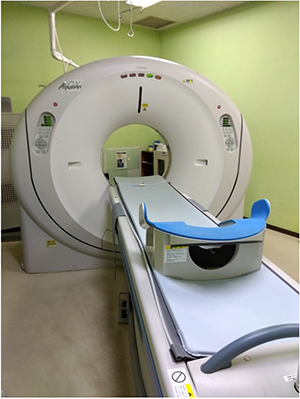

CT検査

CT検査

当院ではCANONメディカルシステムズ社の「Aquilion CX」を使用しております。

CT検査は数十から数百枚の体を輪切りにした画像を作成して医師が診断を行います。レントゲンに比べて病気の発見率があがります。

当院の健診のCTでは胸部CT、腹部CT、内臓脂肪CTを受けることができます。

どの検査も入室から退室まで5分程度で当日検査の申し込みも可能です。